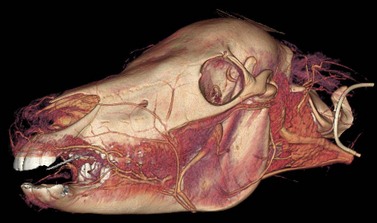

When exposing bone overlying the apex of the mandibular 1st molar (i.e., Triadan 309 or 409), care should be taken to avoid damaging the facial artery and vein and the parotid salivary duct, which cross the lateral surface of the mandible along the rostral border of the masseter muscle close to the site of osteotomy (Fig. 20.40). Reflecting these structures away from the site of trephination may be necessary. When exposing bone overlying the apex of a maxillary premolar (i.e., Triadan 106–108 or 206–208), care should be taken to avoid damaging the infraorbital nerve and facial artery and vein, which lie in close proximity to the site of osteotomy. The apex of any one of the three maxillary premolars is exposed by removing the external lamina of the maxilla overlying it, usually with a trephine. The apices of the maxillary molars (i.e., Triadan 109–111 or 209–211) reside within the paranasal sinuses (Fig. 20.41) and can be exposed through a trephine hole or through an osteoplastic flap into the paranasal sinuses.

image

Fig. 20.40 Computed tomographic image of a head showing the facial artery and vein and salivary duct that course along the rostral border of the masseter muscle.

(Image is courtesy of Luis Velazquez, University of Mexico.)